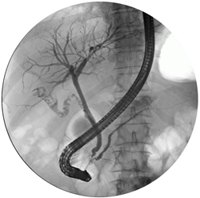

ERCP (Endoscopic Retrograde Cholangio-Pancreatogram) is a technique of examining the small tubes (called ducts) that drain the liver, pancreas and gall bladder.

The aim of the procedure is to pass a small plastic tube into the ducts to inject radio-opaque dye and take x-rays. This plastic tube (cannula) is passed through the channel of a flexible tube called a Duodenoscope. The Duodenoscope allows full colour inspection of the duodenum and opening of the bile duct.